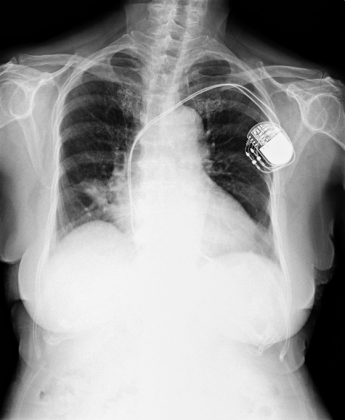

異常胸部X光影像

醫學影像..X光影像